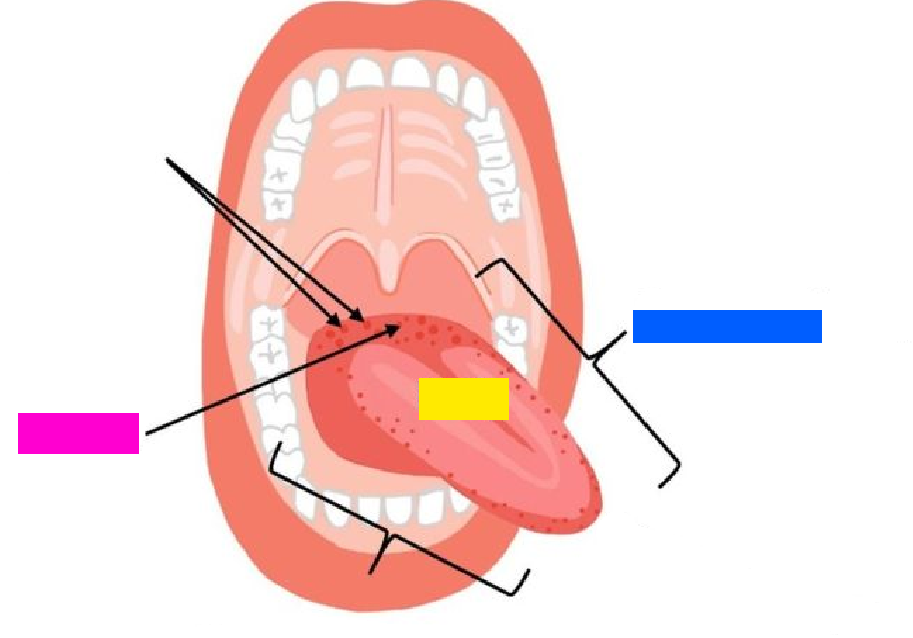

green highlight

Dorsum of tongue

blue box

Body of tongue

yellow box (referencing a section of the tongue)

Root of tongue

pink box

Papillae

(general term)

Lingual frenulum

Openings of submandibular ducts